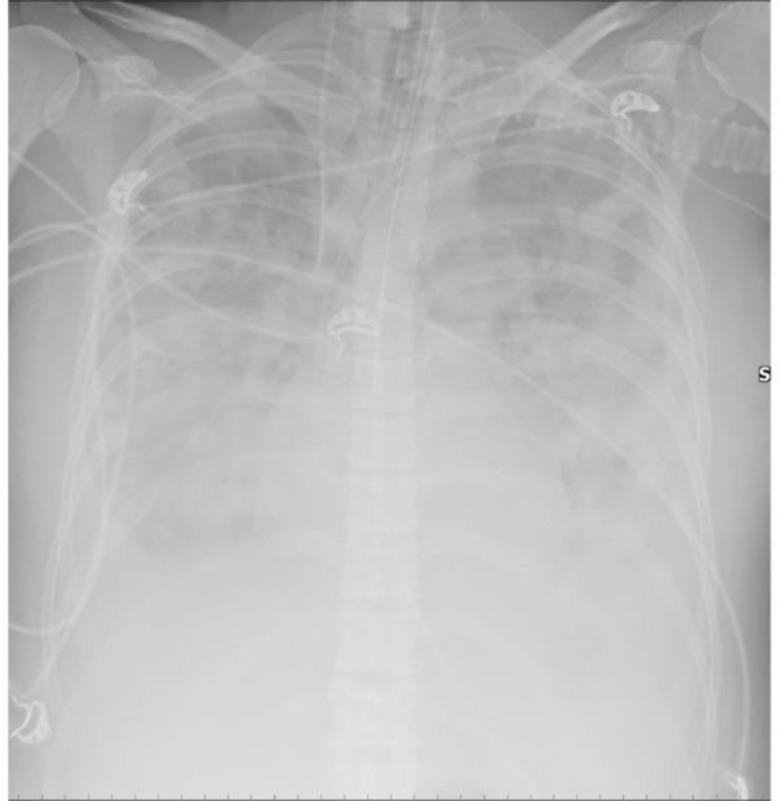

We describe the case of a patient with acquired immunodeficiency syndrome (AIDS) with rapidly worsening dyspnoea and clinical signs suggestive of acute respiratory distress syndrome (ARDS). Despite initial concerns for ARDS, autopsy revealed an advanced-stage, aggressive lymphoma as the underlying cause. This case highlights the challenge of differentiating ARDS from lymphoma in AIDS patients, especially when atypical radiologic findings, such as nodular opacities, are present.

我们描述了一例获得性免疫缺陷综合征(AIDS)患者的病例,该患者呼吸困难迅速加重,并有提示急性呼吸窘迫综合征(ARDS)的临床体征。尽管最初怀疑是ARDS,但尸检显示潜在病因是晚期侵袭性淋巴瘤。该病例突出了在艾滋病患者中区分ARDS和淋巴瘤的挑战,特别是当出现如结节状混浊等不典型放射学表现时。